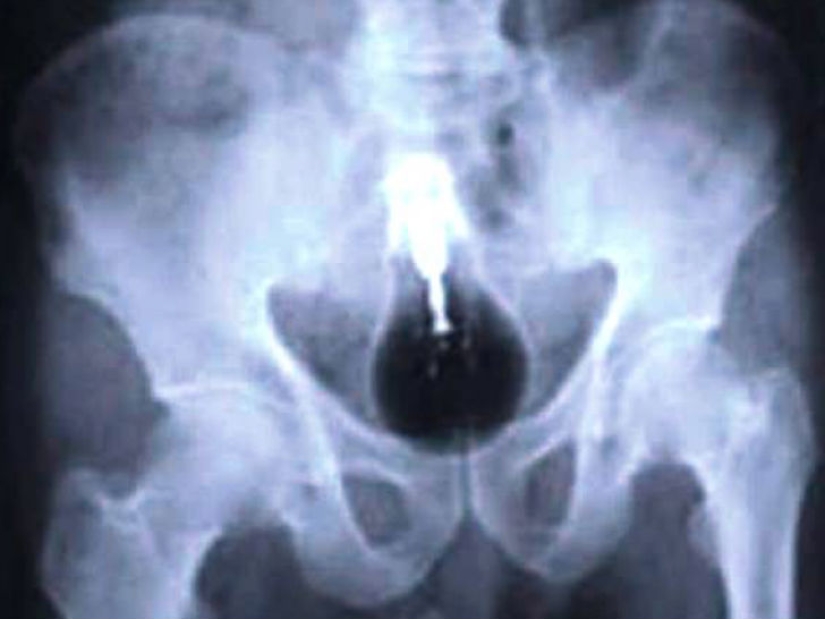

Aquí, tal vez, solo los niños tragan baterías. Radiografía de un bebé de 13 meses.